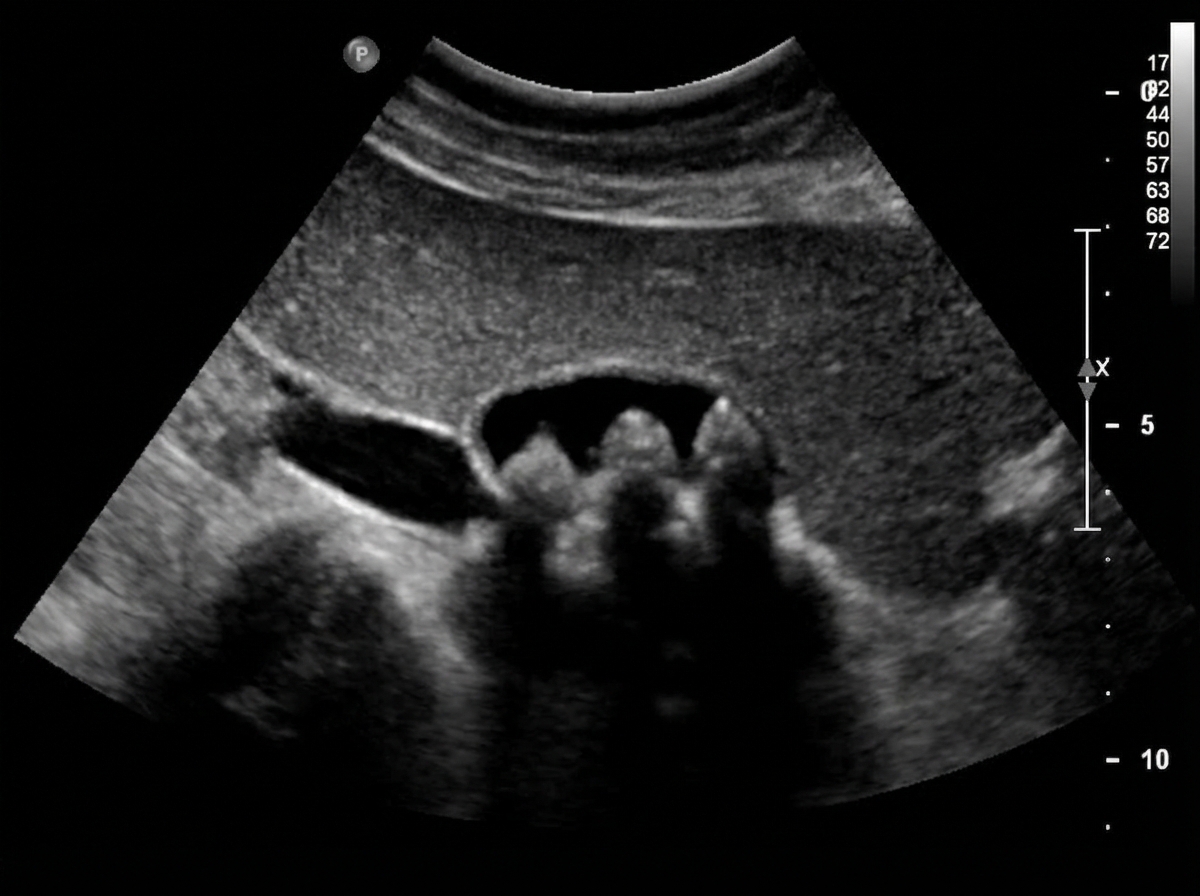

A 64-year-old man presents to the outpatient clinic because of abdominal pain. He reports that for the last few months, he has had postprandial pain that is worsened by spicy foods. He states that the pain is often located in the right upper portion of his abdomen and feels like it's traveling to his shoulder blade. These episodes are sporadic and unpredictable. He denies any fevers. Physical examination shows no abnormalities. Abdominal ultrasound is shown. Which of the following is the best treatment for this condition?